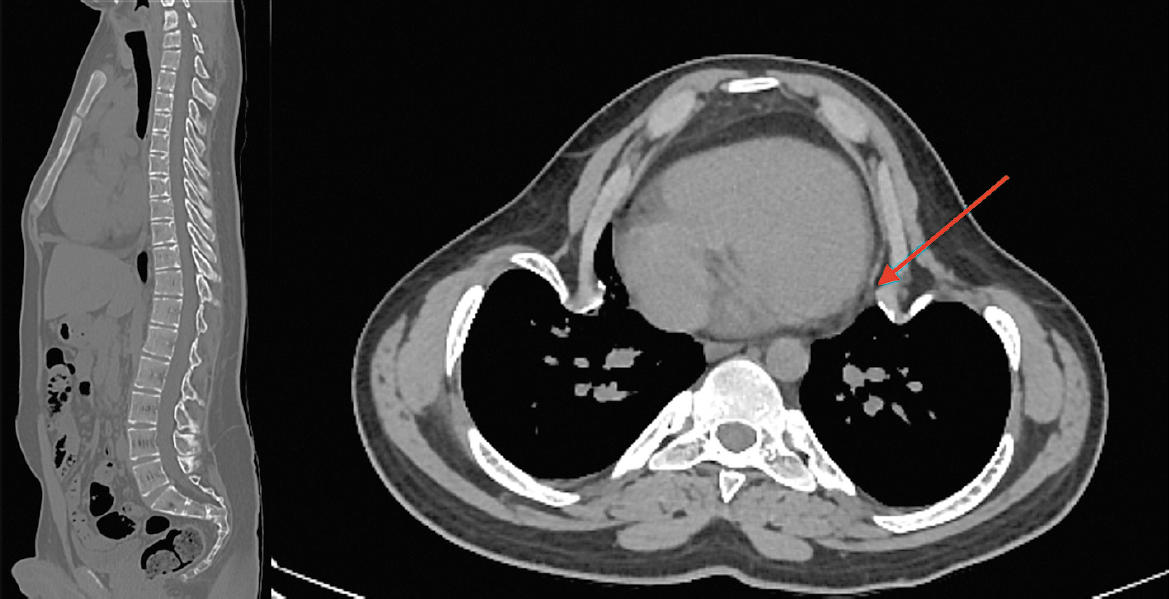

При исследовании состояния костной системы выявлено повышение маркеров костного ремоделирования: остеокальцин – 92,38 нг/мл (норма 24–70), С-концевой телопептид коллагена I типа – 1,39 нг/мл (норма 0,01–0,7). По результатам мультиспиральной компьютерной томографии грудного и поясничного отделов позвоночника отмечается выраженная кифосколиотическая деформация с прилежанием ребер к перикарду правого предсердия (Рис. 2).

Рис. 2. МСКТ грудного и поясничного отделов позвоночника.

Описание: выраженная кифосколиотическая деформация с прилежанием ребер к перикарду правого предсердия.